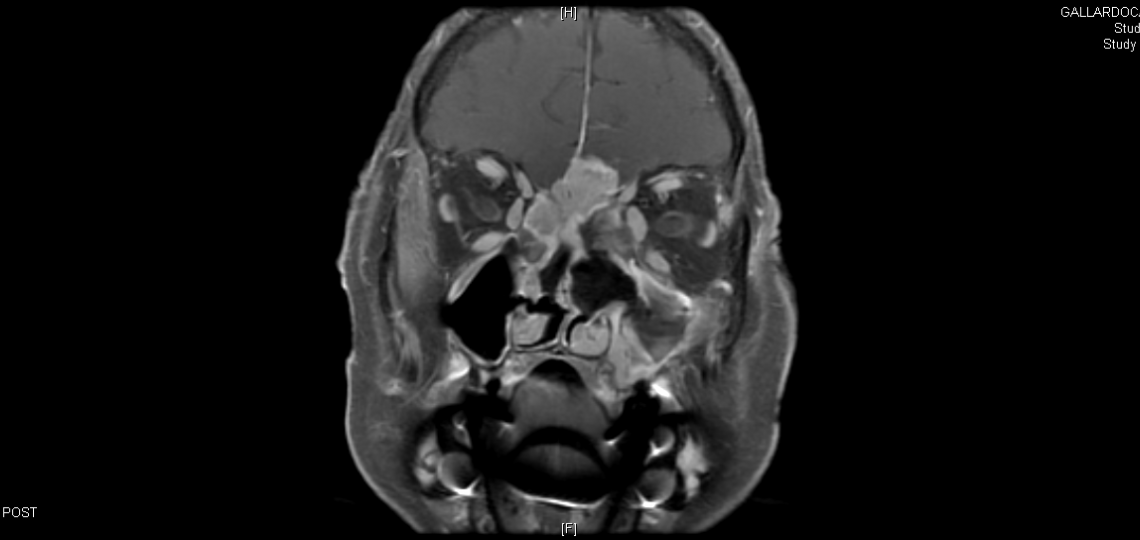

Nose and Sinus Tumors

Tumors in the nose and sinus are close to important structures including the eye, the brain, major nerves and arteries. Treatments for cancers in this area need to target the tumor and still preserve function. Each approach, whether it is a combination of surgery, radiation or chemotherapy, is designed to return the patient to their preoperative functioning and lifestyle while achieving the best possible outcome.